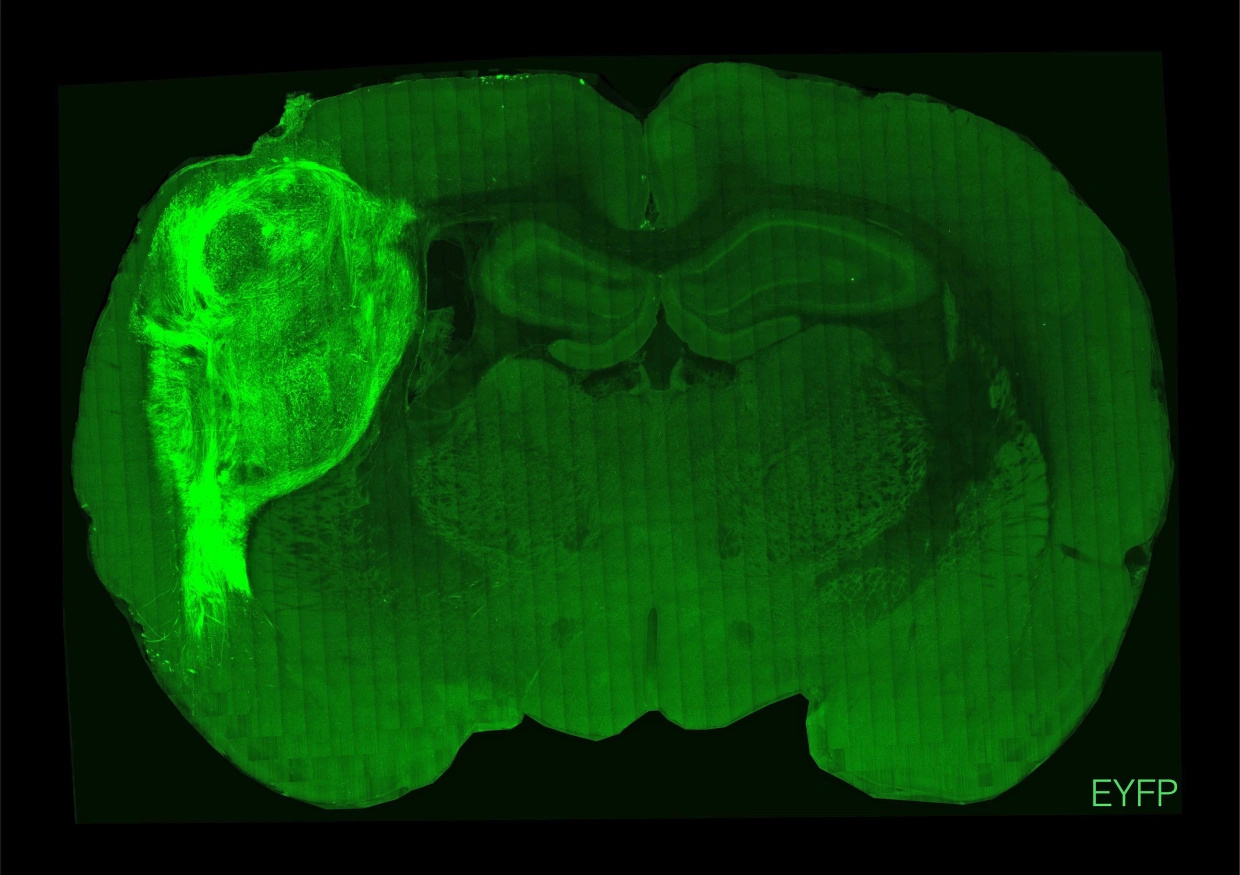

據稱,人體組織植入鼠腦後,在8個月內生長至較本來大5倍,而實驗鼠並無出現癲癇等健康問題,逾70%老鼠接受移植後一年仍然存活。這項聽來似恐怖片情節的實驗,目標並非要培育「科學怪鼠」,而是藉此研究精神病、自閉症、柏金遜症及腦退化症等。有專家指類似研究或有道德爭議,例如「老鼠胚胎注入多少人類細胞,才仍會繼續被稱為老鼠呢?」但強調若可以救人的話,應繼續研究。

螢光位置是植入鼠腦的人腦組織。(互聯網)